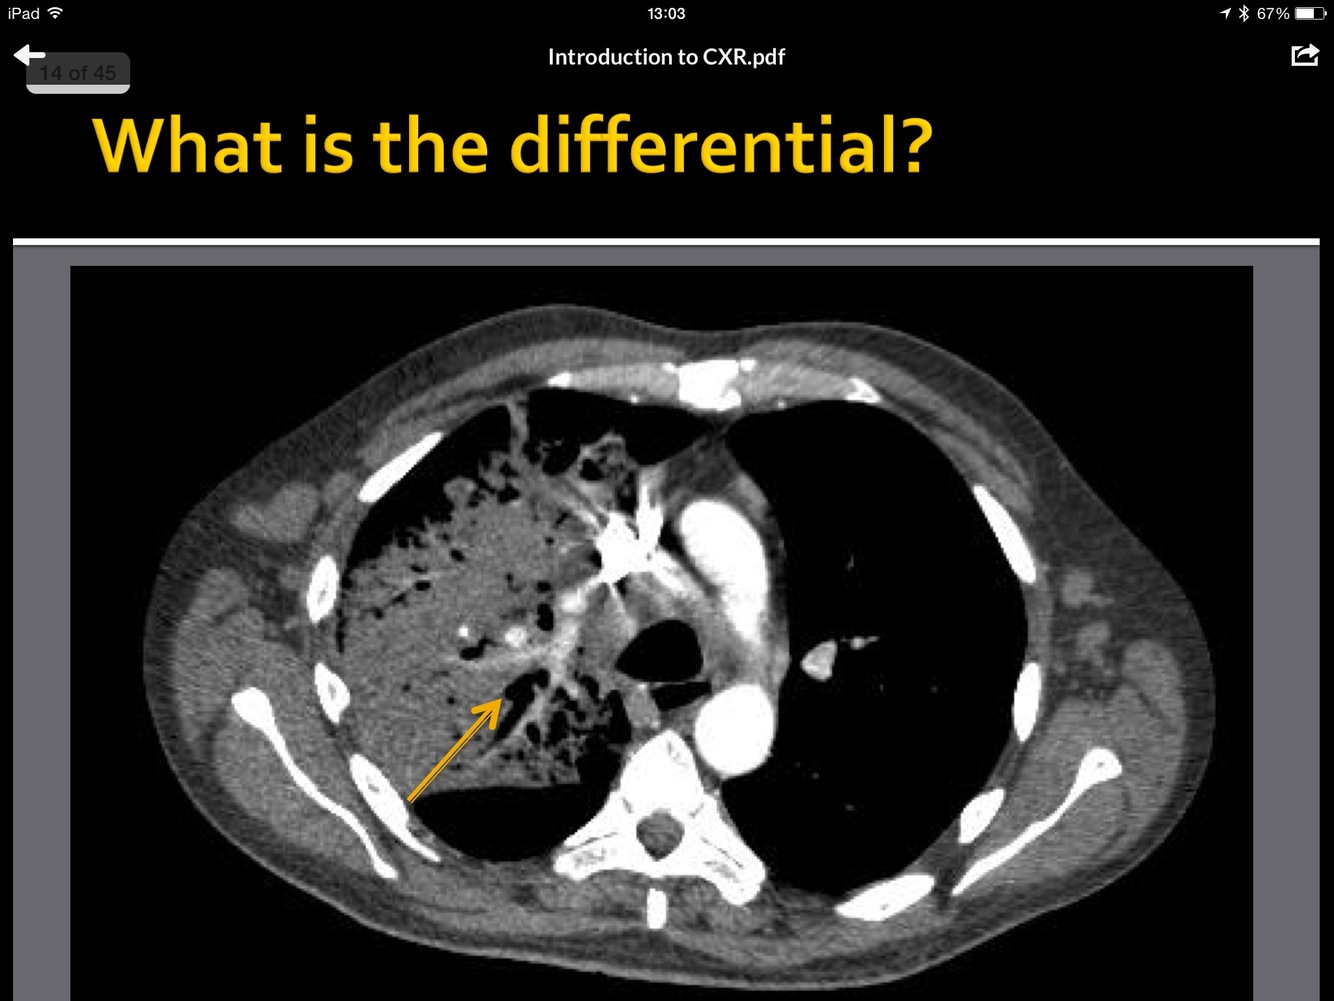

What is the pathology here?